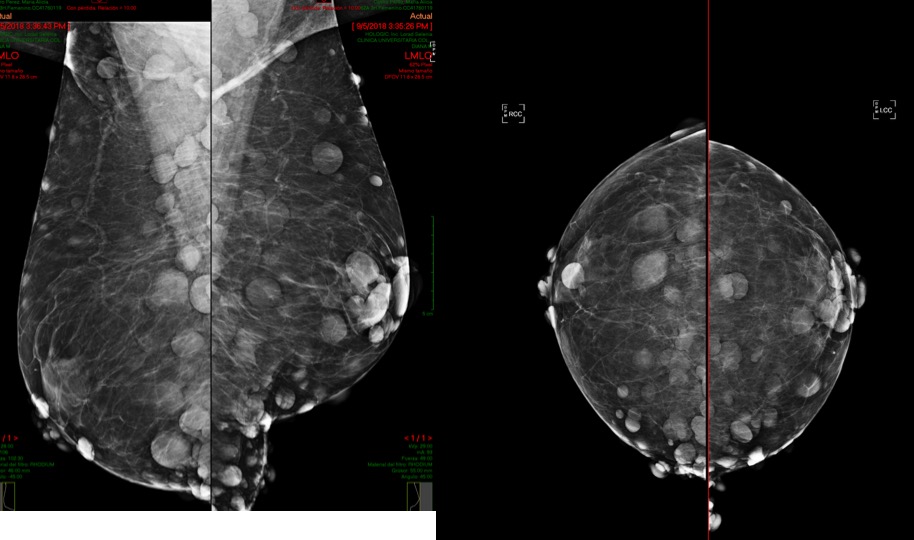

Mujer de 57 años.

lunes, 17 de septiembre de 2018